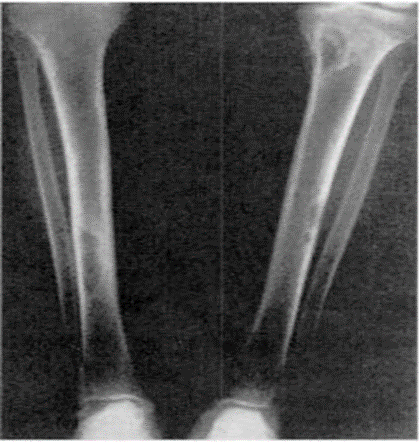

Sümükdə baş verən osteodistrofiyanın mənşəyinin paratiroid olduğunu aydınlaşdırmaq üçün rentgenoqrafiya əsas metodlardan biridir (Şəkil 4).

Şəkil 4. Sümüklərdə osteoporoz

Sümükdə baş verən dəyişikliyi şərti olaraq 3 qrupa bölmək olar:

• I tip klassik forma. Osteoporoz fonunda barmaq falanqalarında sümüküstlüyünün altında, sümüyün qabıq qatının parçalanması görünür. Bəzən seçici olaraq ikinci, üçüncü falanqa və bəzən də üçüncü falanqanın distal hissəsi parçalanmaya məruz qalır. Xarakterik əlamətlərdən biri rentgenoloji müayinədə barmaq falanqalarında “sümük şişlərinin” görünməsidir. Bunlar adətən çoxsaylı olur və skeletin müxtəlif nahiyələrində, ən çox da ətrafların borulu sümüklərində epifiz və metafiz sərhədlərində müşahidə olunur. Aşağı döş və bel fəqərələrinin osteoporotik zədələnməsi onların yastılaşması və onurğanın deformasiyasına səbəb olur (kifoz, skalioz).

• II tip osteoporotik forma. Bu generalizə olunmuş osteoporoz şəklində meydana çıxır.

• III tip Paget forma. Bu zaman kəllə sümüklərinin kompakt qatı qeyri-bərabər qalınlaşır. Kraniumda subperiostal rezorbsiya və sklerozun nəticəsi olaraq “duz-bibər” mənzərəsi əmələ gəlir. Bu zaman borulu sümüklərin kompakt maddəsi nazikləşir, falanqalar qəhvəyi şiş adlandırılan bir forma alır. Sümük toxuması fibroz toxuma ilə əvəz olunduqca oraya qansızma ilə bərabər hemosiderin də toplanır. Xəstələrin 30%-də osteopeniya əmələ gəlir.